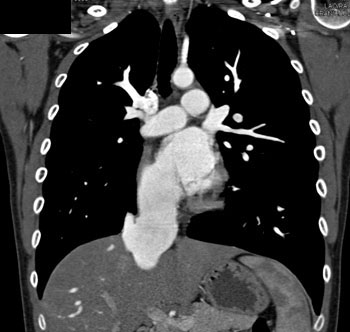

|  | Question 4: 20 year old male with a history of mitral valve prolapse and increasing exertional dyspnea and palpitations. What’s the diagnosis? |